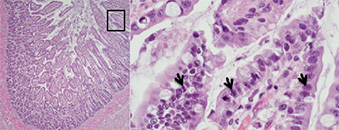

Een 17 dagen oude pup ging dood na klachten van diarree. Op 15 dagen leeftijd ontwikkelde het dier klachten van diarree en niet willen drinken; meerdere nestgenoten hadden last van diarree.